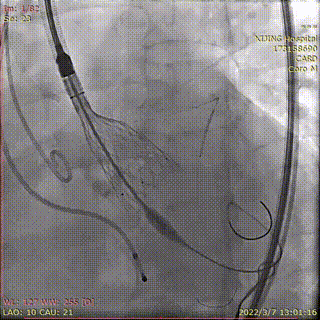

预置4.0*35mm冠脉支架左冠保护并根部造影

22mm球囊预扩张,无漏